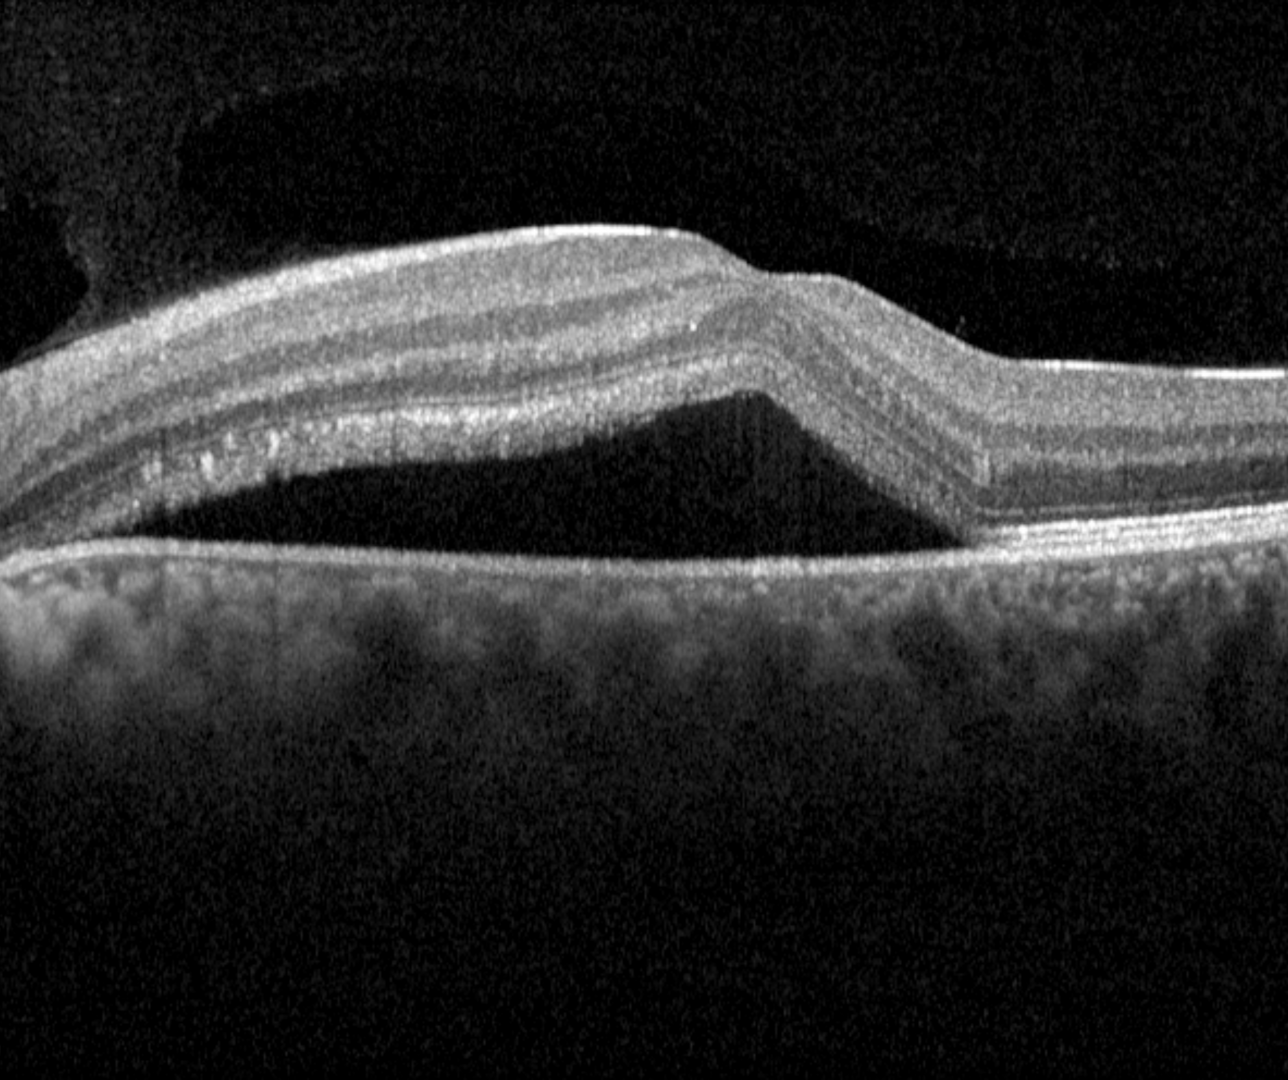

OCT shows a well defined, dome-shaped, serous retinal detachment usually associated with a serous PED. The retinal layers are otherwise undisturbed in acute presentations, however, in cases of persistent subretinal fluid, elongation of the photoreceptor outer segments, subretinal fibrin, and subretinal yellowish dots can occur.

Spectralis OCT volume and line scans (left macula)

Spectralis OCT volume and line scans (left eye)